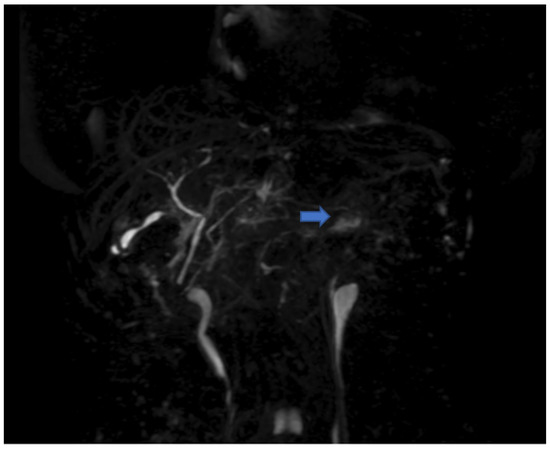

2. Case Presentation and Results